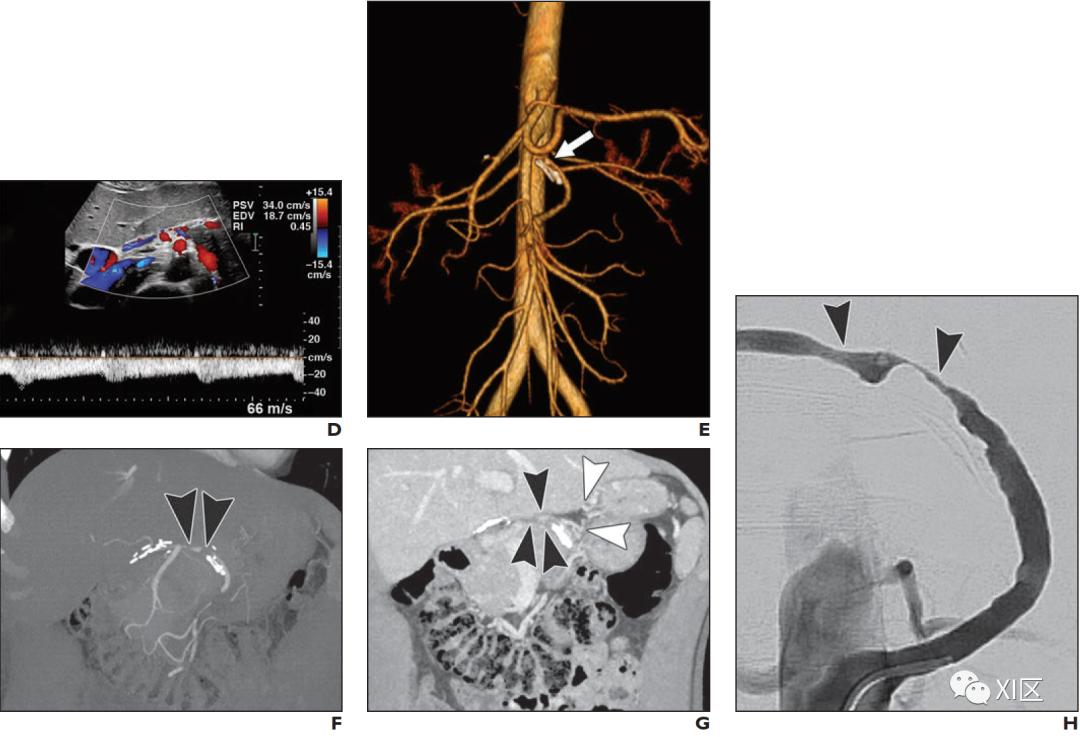

肾血管性高血压

儿童继发性高血压比成人更常见,肾血管狭窄的发生率估计约占小儿高血压病例的5-25%。在主动脉缩窄和肾实质疾病之后,肾血管疾病是小儿继发性高血压的第三大最常见原因。许多潜在疾病可能导致儿童肾血管异常,其中许多是系统性疾病,并导致复杂的多系统疾病。这些包括纤维肌增生异常,中主动脉综合征,Williams综合征,Turner综合征,母斑病如神经纤维瘤1型(NF1)和结节性硬化症,以及血管炎(图9)。这些疾病中许多疾病的影像学特征重叠,并且与其他临床特征(例如NF1病例中的咖啡色皮肤表现)的相关性对于最终诊断通常是必需的。

DSA是诊断肾动脉狭窄的参考标准,具有小血管效应和立即血管成形术的潜力。多普勒超声通常用作小儿肾血管性高血压的一线筛查试验,其特异性为94–95%,但敏感性仅为65%。相比之下,CTA在儿科人群中显示出88%的敏感性。MRA对肾动脉狭窄具有较高的敏感性和特异性,而使用钆造影剂则更为如此,但对于肾功能不全的患者,未增强序列具有合理的准确性。然而,CTA是非侵入性的,在大多数情况下无需镇静即可进行,并且已被证明具有与成人DSA相当的准确性。此外,CTA可能显示出非血管性高血压原因,例如肾脏或肾上腺肿瘤。

肾血管疾病的CTA表现包括动脉不规则,串珠样轮廓和狭窄(图9)。儿童的大多数肾动脉狭窄累及主要,附属或节段性肾动脉。在CTA上很难显示二级分支远端的实质内动脉,而DSA可能对于明确排除肾脏实质内狭窄是必要的。狭窄的继发体征可能包括狭窄后扩张,侧支动脉的存在,局灶性实质性灌注缺陷,不对称的肾X线造影图和实质性瘢痕形成(图9)。